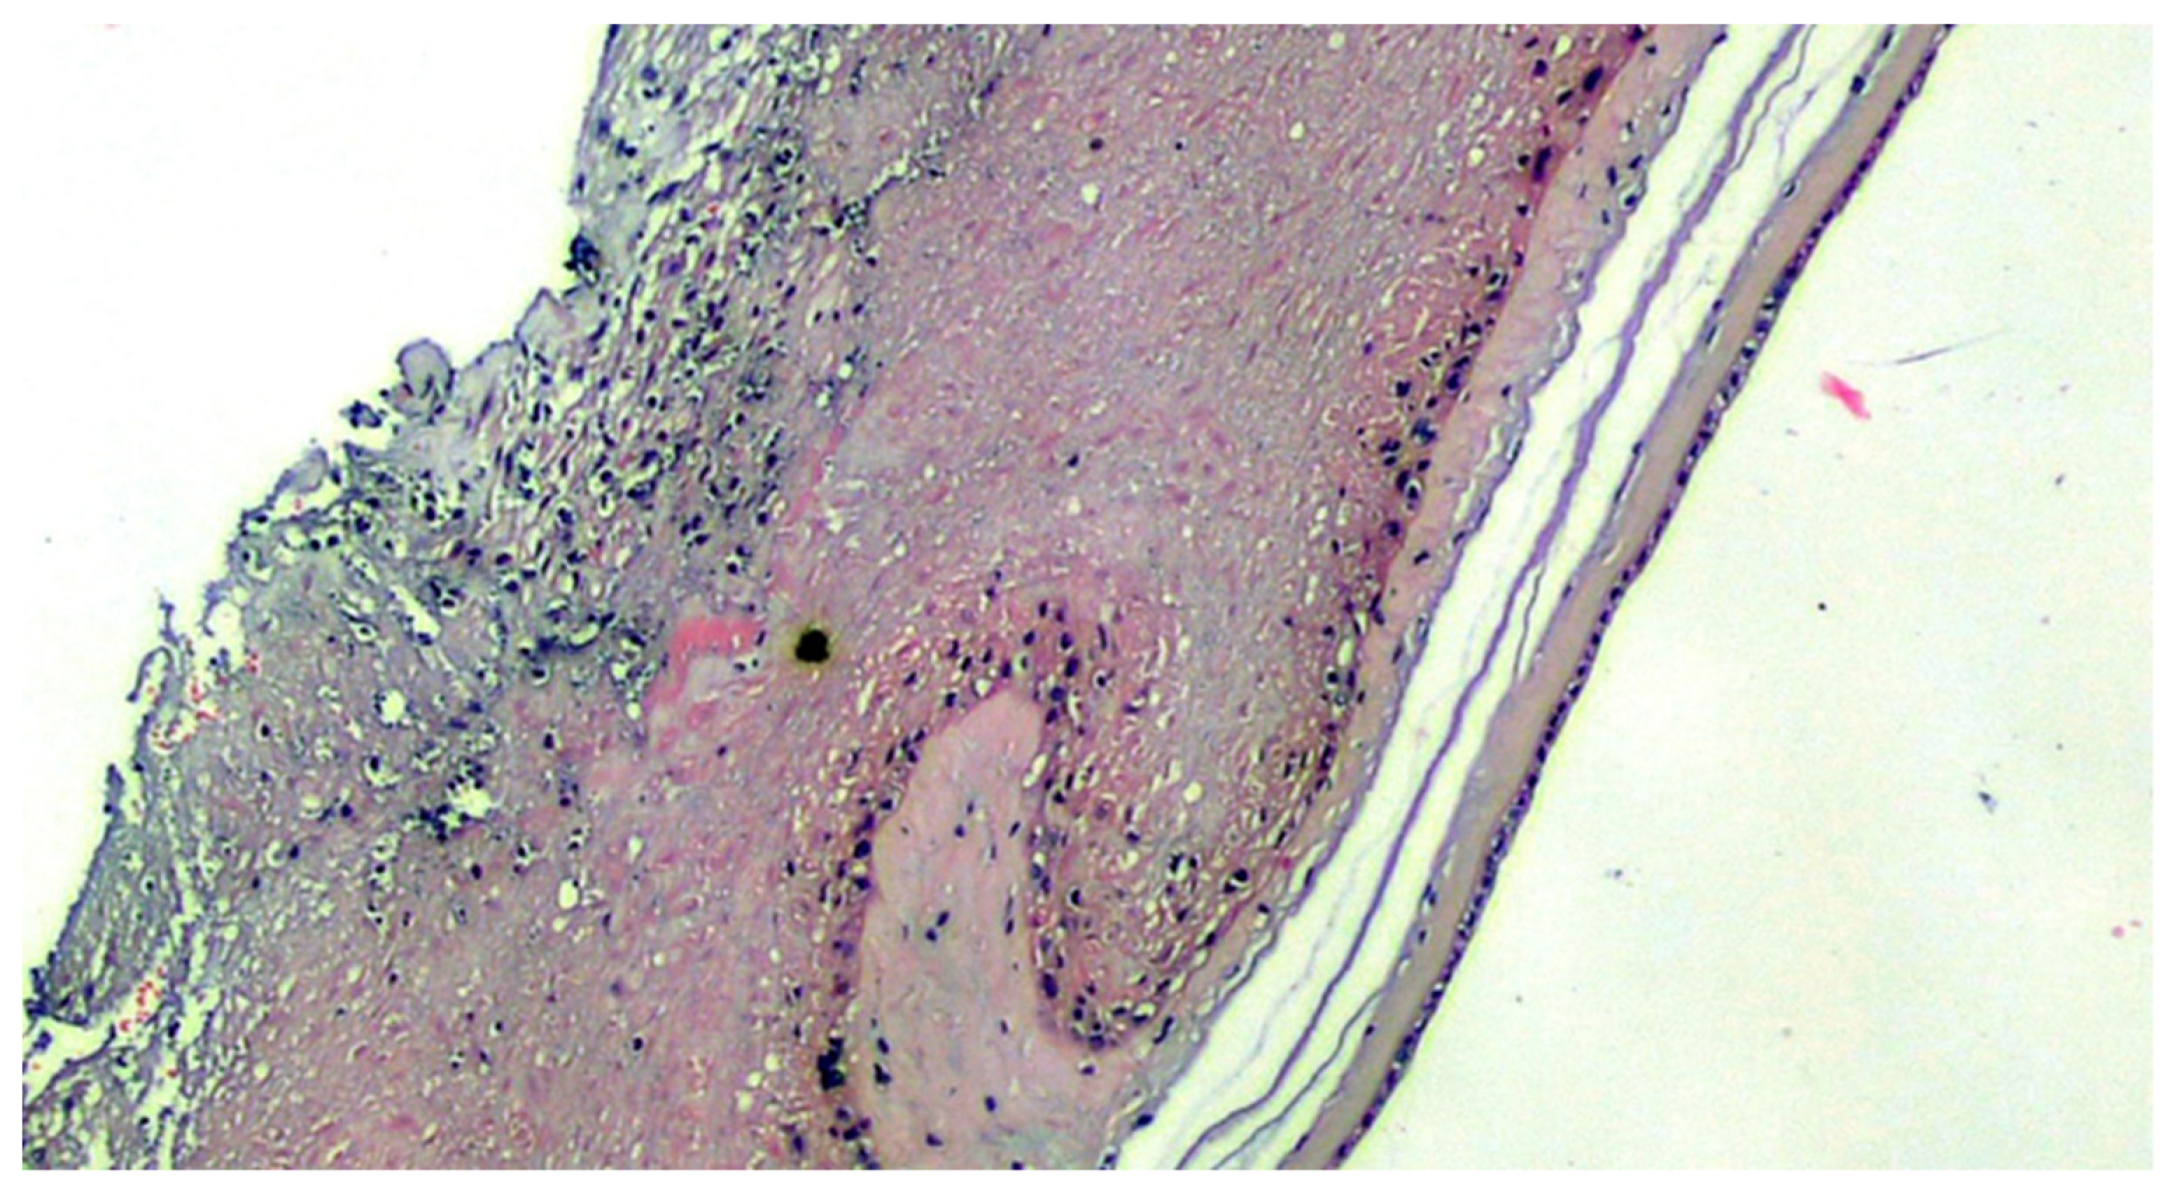

Figure 1.

COVID-19-positive mother placenta. Terminal chorionic villi with poor vascular component (distal hypoplasia of the villi due to early maternal malperfusion) with increased syncytial nodes. Some villi show a deposition of fibrin in the intervillar space with progressive reduction of the villi (H&E, Hematoxylin and Eosin, 100×).

Figure 3.

Basal deciduitis with a little trophoblastic component (superficial implant) and with few inflammatory cells (H&E, 200×).

Figure 4.

Deciduitis with large foci of necrosis and massive infiltration of mainly granulocytic inflammatory elements (acute deciduous, H&E, 200×) in the placenta of a COVID-positive mother.